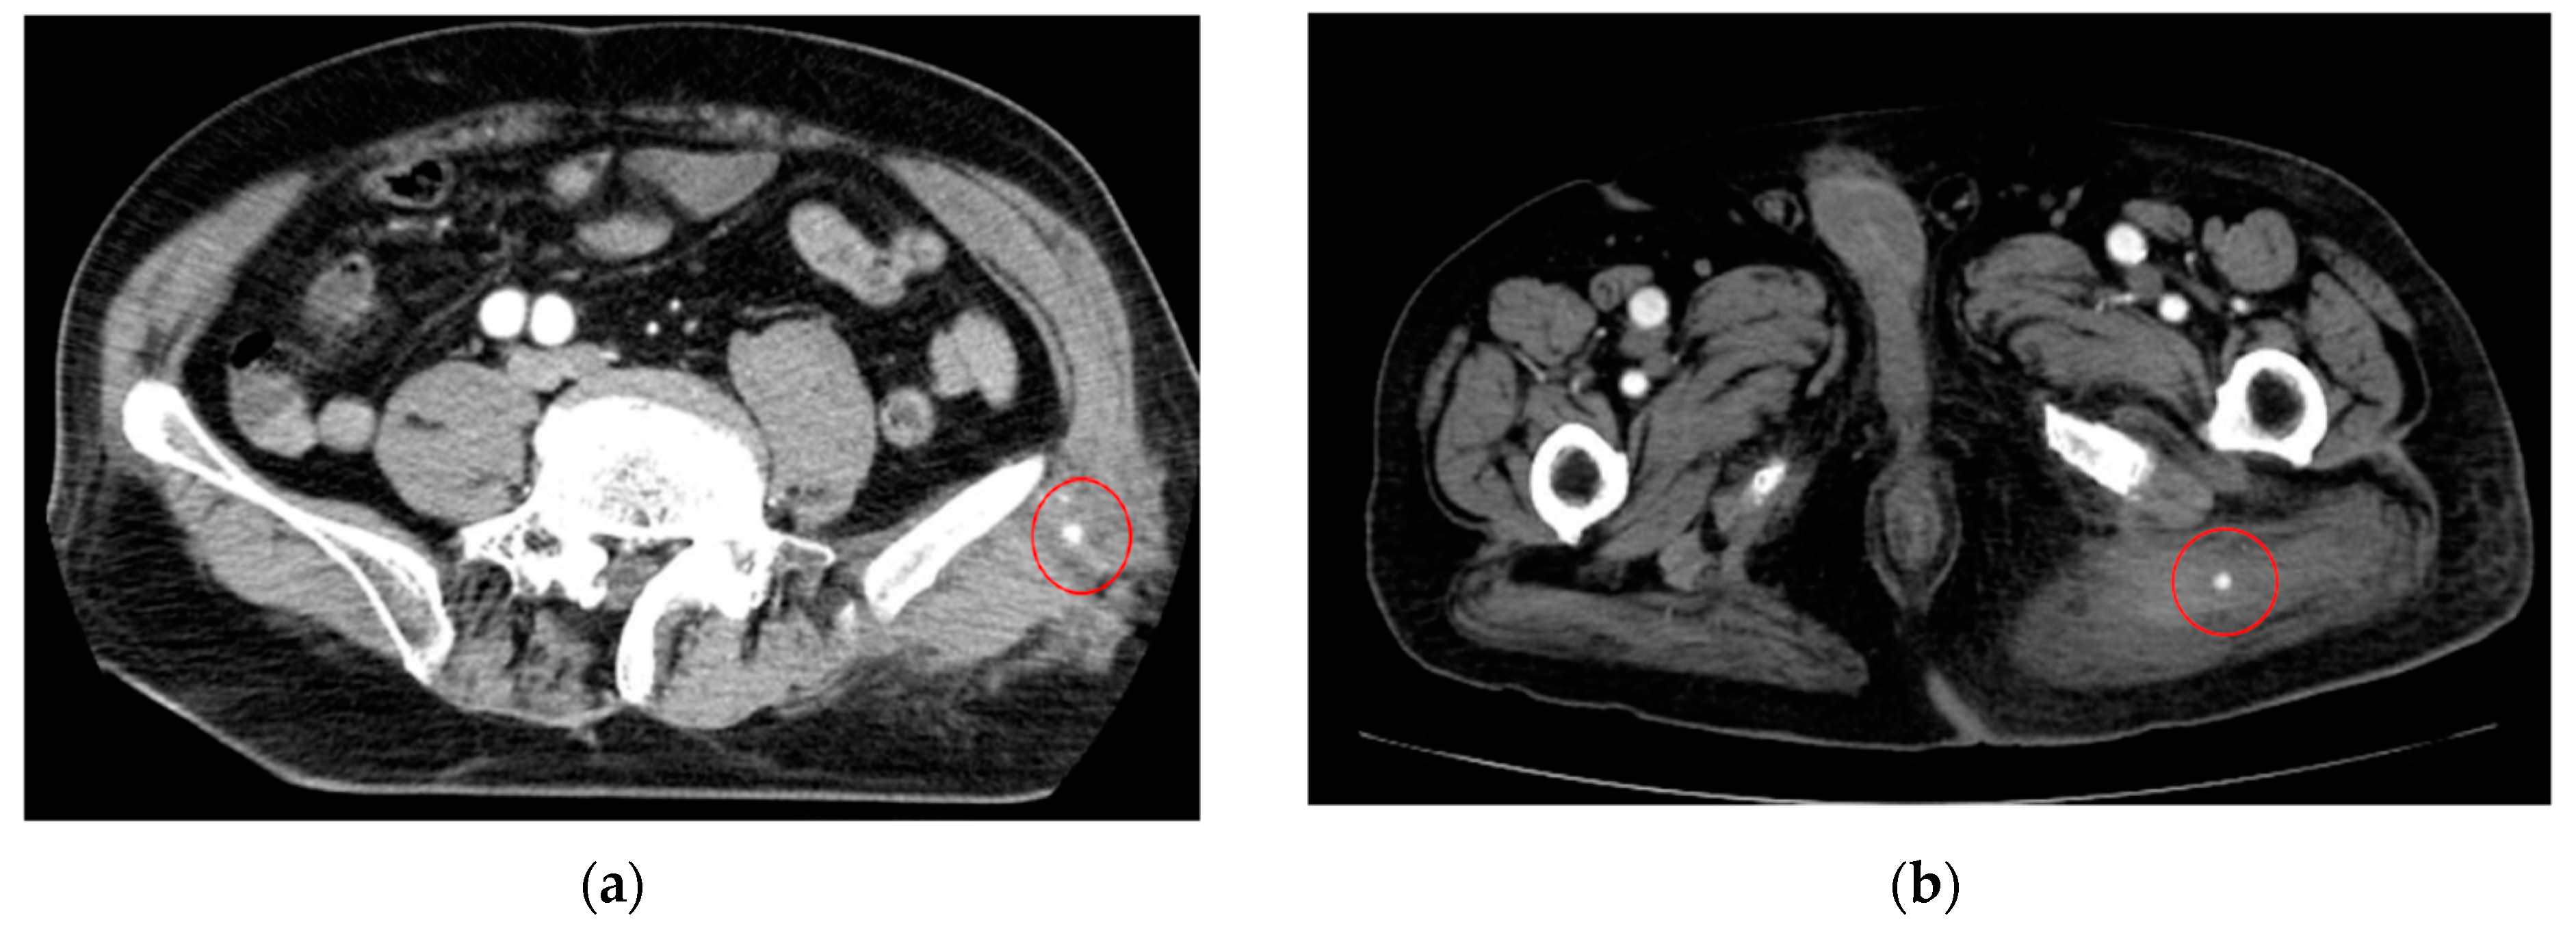

- AI for Image Analysis: AI-based image analysis algorithms can enhance the detection and diagnosis of extravasation events in imaging studies, such as ultrasound, MRI, and CT. These algorithms can automatically identify subtle signs of extravasation, assist healthcare providers in interpreting the imaging findings, and facilitate a timely intervention. This suggestion is subsequently extended as a separate discussion.

- Albano, D.; Benenati, M.; Bruno, A.; Bruno, F.; Calandri, M.; Caruso, D.; Cozzi, D.; De Robertis, R.; Gentili, F.; Grazzini, I.; et al. Imaging side effects and complications of chemotherapy and radiation therapy: A pictorial review from head to toe. Insights Imaging 2021, 12, 76. [Google Scholar] [CrossRef] [PubMed]